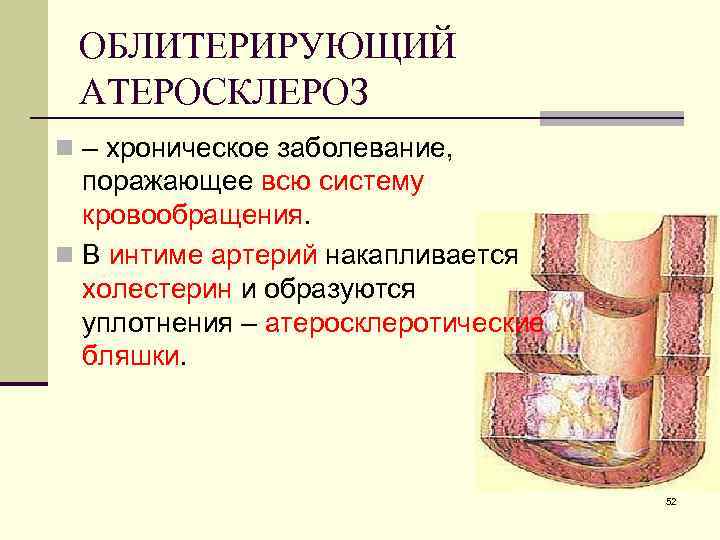

ОБЛИТЕРИРУЮЩИЙ АТЕРОСКЛЕРОЗ n – хроническое заболевание, поражающее всю систему кровообращения. n В интиме артерий накапливается холестерин и образуются уплотнения – атеросклеротические бляшки. 52